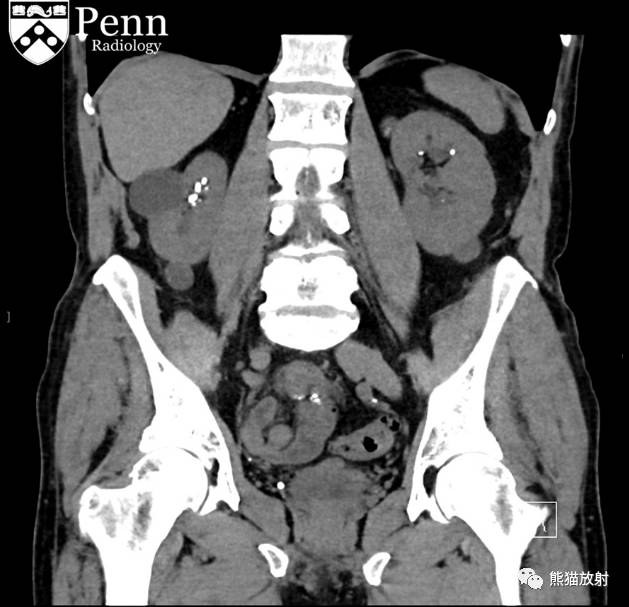

History: A 75-year-old man with a chronic history of microhematuria was referred for a CT urogram by his urologist.

病史:75岁男性,长期镜下血尿,泌尿外科医生建议其行CTU检查。

Scout, coronal precontrast, axial nephrographic/excretory phase images, and volume-rendered coronal reconstructions of the left and right kidneys are shown below.

定位像、冠状平扫、轴位排泄期图像及左、右肾冠状VR重建如下所示。

CT urogram (2017): Noncontrast images demonstrate multiple bilateral nonobstructing renal calculi, the largest measuring 6 mm in the right kidney. Some of the calcifications could represent nephrocalcinosis — for example, those in the upper pole of the right kidney. The kidneys show symmetric enhancement without suspicious renal mass. Multiple bilateral exophytic simple renal cysts are noted, the largest in the midpole of the right kidney measuring 3.6 x 4.3 cm. There are additional subcentimeter low-attenuation lesions that are too small to characterize. There is a “paintbrush sign” appearance to the renal medullae in keeping with a history of medullary sponge kidney. There is mild bladder wall thickening and trabeculation that may be related to chronic outlet obstruction. Further evaluation is deferred to cystoscopy.

CTU:CT平扫可见双肾多发非梗阻性肾结石,右肾最大者直径约6mm,其中一些钙化可能代表肾结石,例如,右肾上极的那些。肾脏对称性强化,未见可疑肾肿物。双肾可见多发单纯性肾囊肿,大者位于右肾中部,大小约3.6 x 4.3 cm;另可见不足1cm的低密度灶,其太小而不能显示。肾髓质表现为“毛刷征”,符合髓质海绵肾。膀胱壁轻度增厚并小梁形成,与慢性流出道梗阻有关。进一步评估需膀胱镜检查。